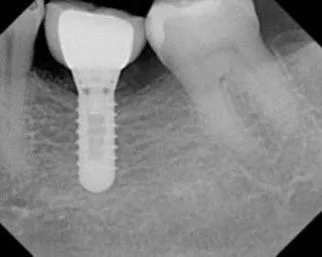

Implant placement with using Sinus Bone Graft

Before

After